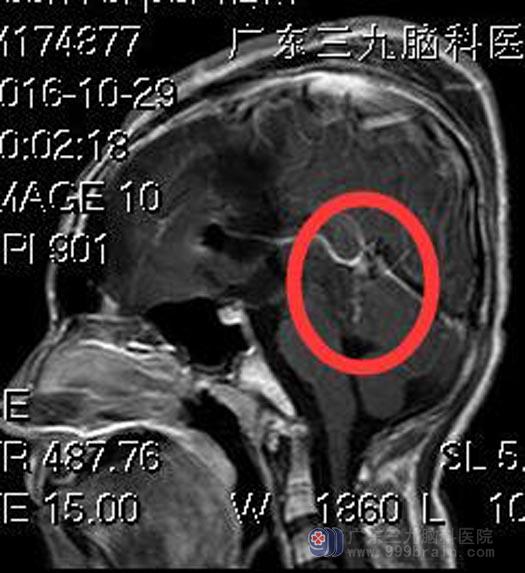

鲁明主任主刀,在全麻下行松果体区肿瘤切除术。术中见肿瘤位于松果体区,呈灰白色(其间夹带部分淡黄色成分),质软,血供一般。显微镜下顺利分块全切除肿瘤,双侧大脑内静脉、大脑大静脉保留完整。术后小凯头痛症状明显好转,康复出院。术后病理结果提示:实体型卵黄囊肿瘤。

▲手术后